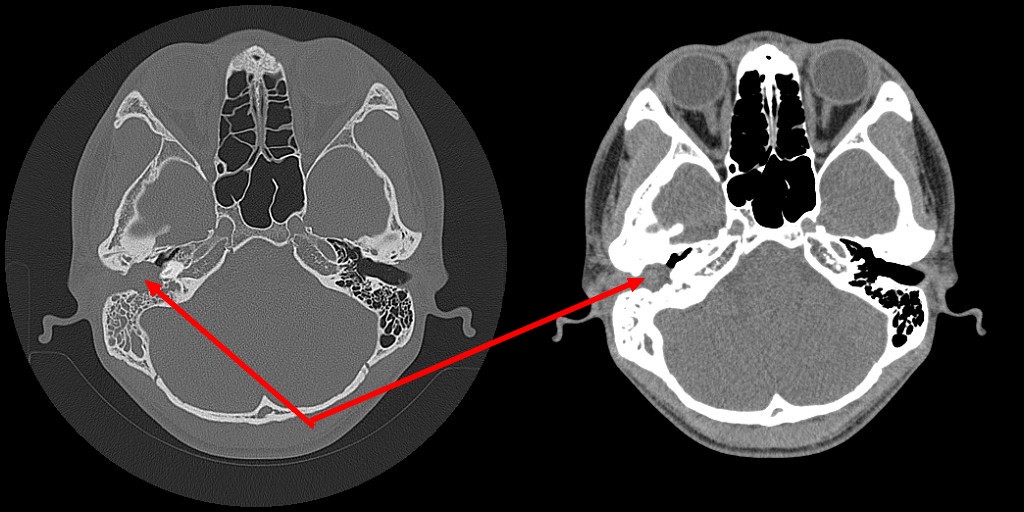

标题: CT25419:男性,18岁。右耳肿、痛5个多月。 [打印本页]

标题: CT25419:男性,18岁。右耳肿、痛5个多月。

右侧中耳乳突炎累及外耳道,鼻咽腺样体肥大。

1)右侧慢性中耳乳突炎并右侧中耳腔及外耳道肉芽肿或胆脂瘤形成。2)鼻咽腺样体肥大。